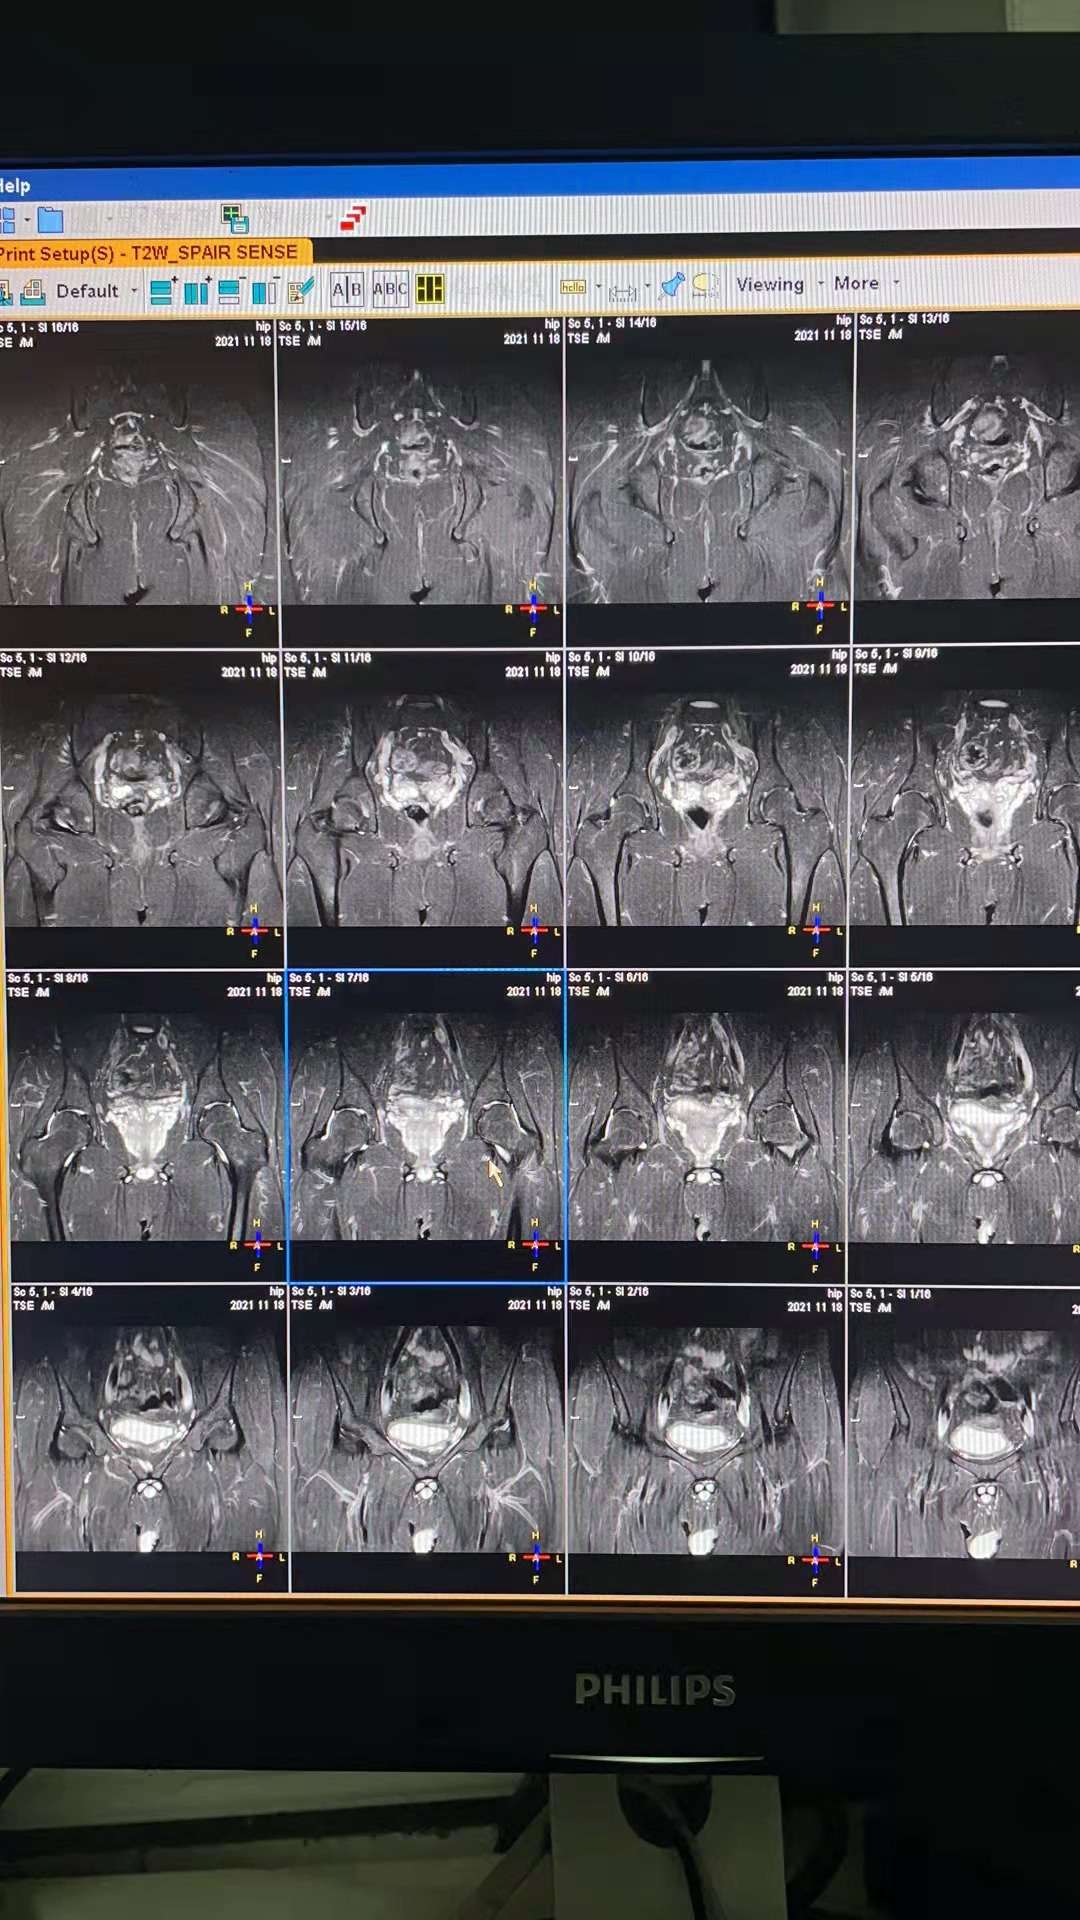

整齐的烈马可是在网上查髋关节积液不都是走路的时候疼吗